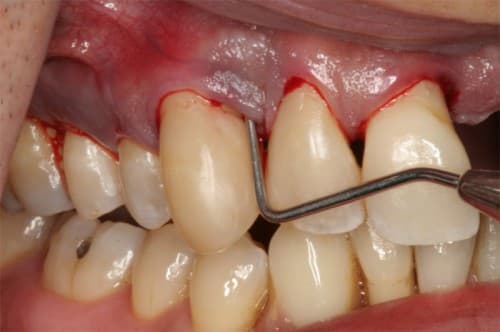

– Khi chải răng hoặc sử dụng chỉ nha khoa để làm sạch, nướu viêm có thể chảy máu dễ dàng hơn so với nướu không bị viêm. Đây là một trong những dấu hiệu rõ ràng của viêm lợi.

– Nướu xung quanh răng bị viêm thường trở nên đỏ và mềm hơn bình thường. Màu đỏ của nướu có thể là một dấu hiệu cho thấy sự viêm nhiễm và sự kích thích của mô nướu.

Bệnh cần được điều trị tránh để xảy ra những biến chứng nặng nề